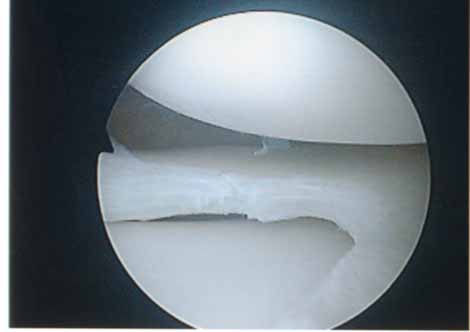

第1段階軟骨形成術

軟骨障害は最初亀裂または剥離で始まります。この状態が第一段階軟骨障害です。このことはあまり一般に知られていません。この最初の亀裂や剥離状態のうちに対処することが最も結果が良好となります。亀裂や剥離が進んでしまうと②の状態になります。